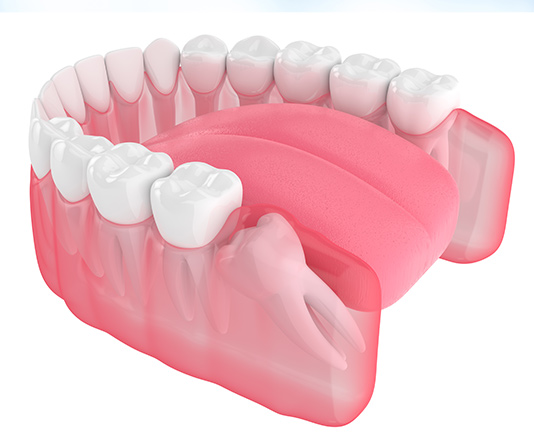

Dental implants restore your entire tooth, from root to crown, by being inserted directly into the socket. To maintain the bone's strength and health and to firmly anchor your new tooth in place, they fuse with the jaw. Implants are durable and frequently maintain their perfect state for a lifetime.